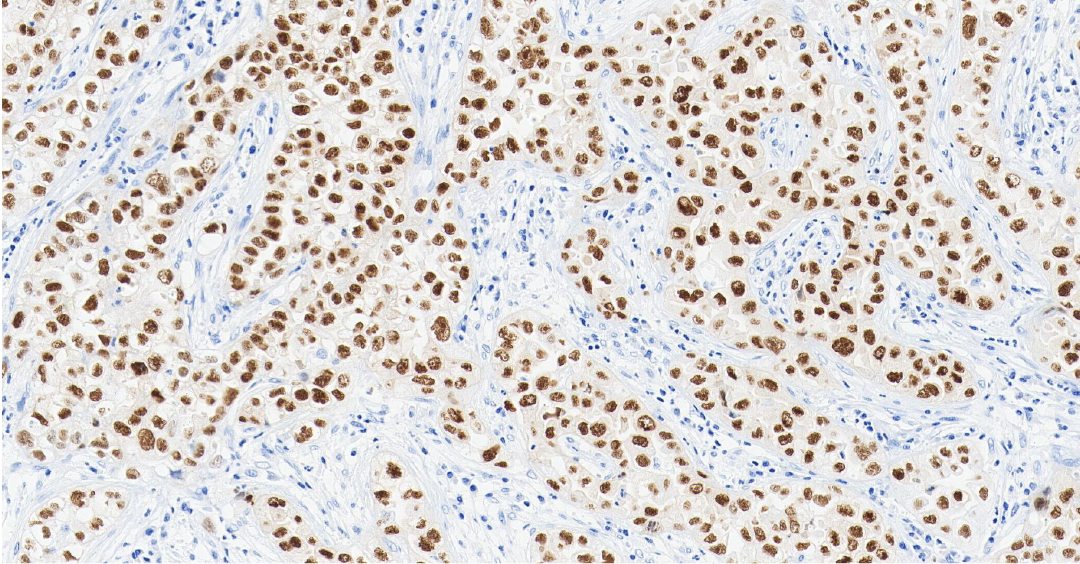

TTF-1

TTF-1 ——甲状腺转录因子-1,属于 NKX2 转录因子家族。

定位: 细胞核。

功能: TTF-1 是调控肺组织和甲状腺器官特异性基因表达的核转录因子,对肺泡上皮细胞的终末分化和表面活性物质的分泌至关重要。

TTF-1 是关键的核转录因子,表达具有高度组织特异性。它在肺腺癌和甲状腺癌中高表达,是诊断这些原发癌的核心标志物 [3] 。 其临床价值在于鉴别转移癌的原发部位:若 TTF-1 阳性,强烈提示肿瘤来源于肺或甲状腺。值得注意的是,肺鳞癌中 TTF-1 通常为阴性,需结合其他标志物来进一步确认[4]。

图 2.人肺癌组织的 TTF-1 免疫组化分析[5]。